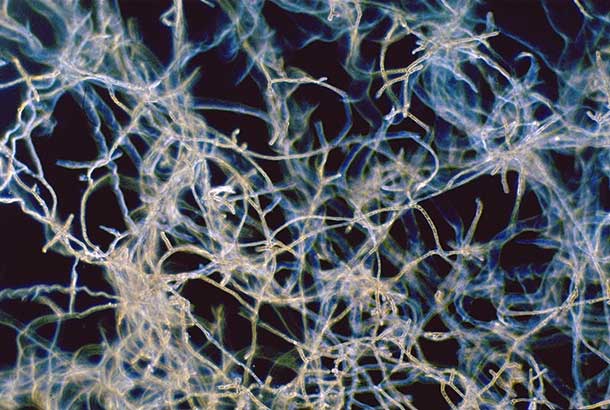

"name": "Fungal Keratitis",

"category": "Cornea",

"detail": "<p><em>Fusarium</em>&nbsp;keratitis,&nbsp;<em>Aspergillus</em>&nbsp;keratitis ,&nbsp;<em>Candida</em>&nbsp;keratitis</p>\n\n<h2>Symptoms</h2>\n\n<ul>\n\t<li>Acute severe pain</li>\n\t<li>Extreme redness</li>\n\t<li>Epiphora and photophobia</li>\n\t<li>No improvement with lens removal</li>\n</ul>\n\n<h2>Signs</h2>\n\n<ul>\n\t<li>Typically unilateral</li>\n\t<li>Localized corneal infiltration, often with feathery margins and elevated edges. Satellite lesions may also be present</li>\n\t<li>Penetration of infiltrate into the stroma with surrounding edema.</li>\n\t<li>Hypopyon</li>\n\t<li>Anterior chamber reaction</li>\n\t<li>Severe hyperemia and possibly lid edema</li>\n</ul>\n\n<h2>Etiology</h2>\n\n<ul>\n\t<li>May follow trauma (generally with plant material) to the cornea</li>\n\t<li>Inappropriate use of care systems (e.g. topping off, poor case hygiene) may result in product contamination by&nbsp;<em>Fusarium spp</em>.</li>\n</ul>\n\n<h2>Prevalence</h2>\n\n<ul>\n\t<li>Very rare</li>\n</ul>\n\n<h2>Differential Diagnosis</h2>\n\n<ul>\n\t<li><a href=\"/condition/2\">Acanthamoeba&nbsp;infection</a></li>\n\t<li><a href=\"/condition/24\">Microbial (bacterial) keratitis</a></li>\n\t<li><a href=\"/condition/20\">Corneal Infiltrates</a>,&nbsp;<a href=\"/condition/6\">CLPU</a>&nbsp;and other&nbsp;<a href=\"/condition/65\">staining patterns</a></li>\n\t<li>See: <a href=\"/condition/66\">Infiltrates and Opacities &ndash; Differential Diagnosis</a></li>\n</ul>\n\n<h2>Management</h2>\n\n<ul>\n\t<li>Cease lens wear immediately</li>\n\t<li>Consider culturing before initiating antimicrobial therapy, particularly for large central ulcers</li>\n\t<li>Instigate topical antifungal treatment</li>\n\t<li>Deeper infections may require systemic antifungal medication</li>\n\t<li>Treatment may be required for several months</li>\n</ul>",